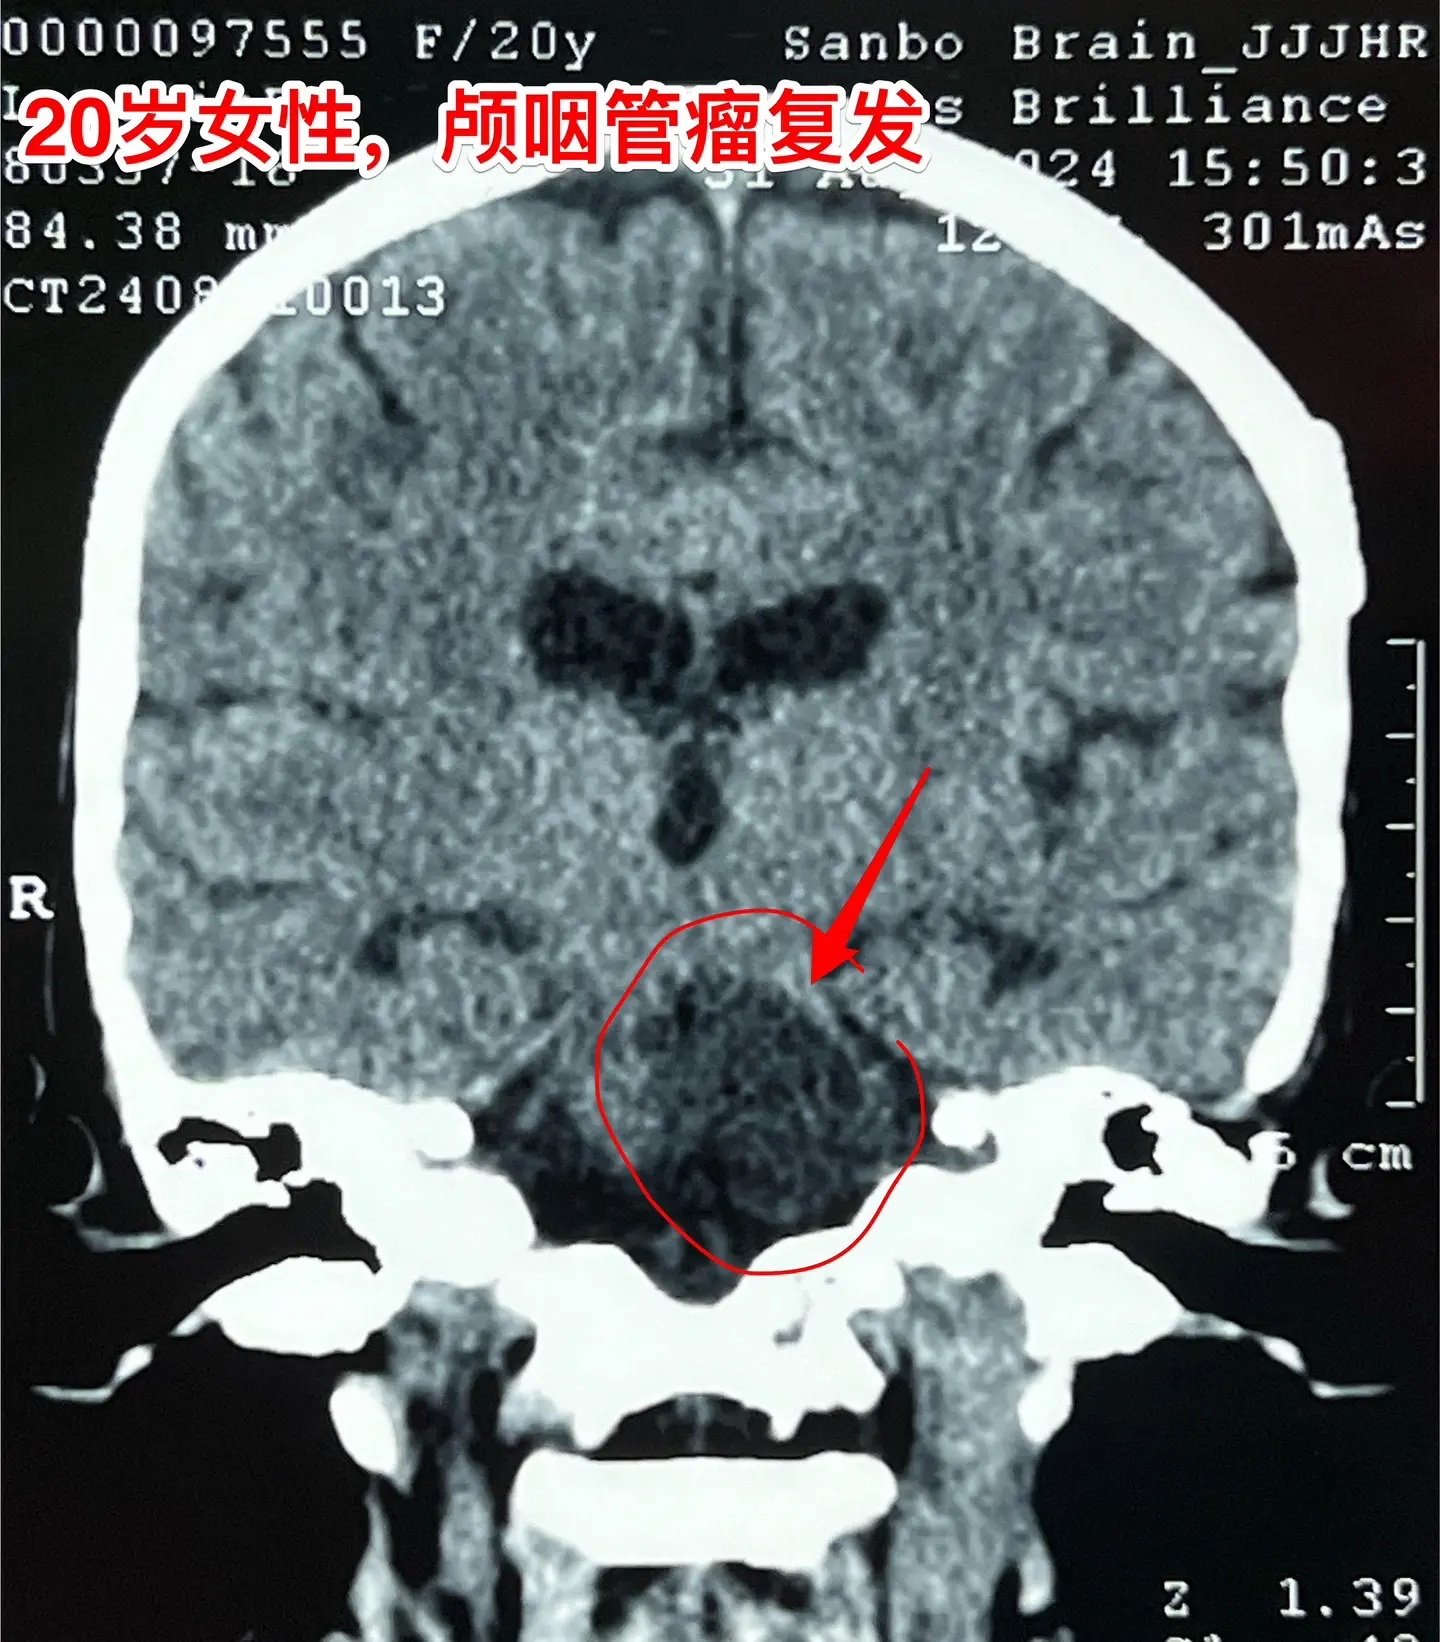

颅咽管瘤第七次开颅手术,恢复顺利。20岁女性,广东省东莞人。不幸的孩子...